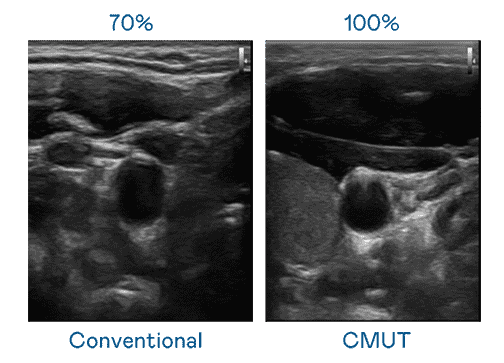

CMUT 技术是一种用电容式微机电元件来产生超音波讯号的技术。。。。与传统 PZT 压电式技术相比,,,,CMUT 频宽增加 30%,,,,更宽频的超音波讯号让影像解析度大幅提升,,是实现高影像品质医疗超音波扫描、、促进精准医疗发展的关键技术。。

超音波影像的解析度高低,,,,首先取决于探头能发出的讯号频宽。。。赏金国际 CMUT 可提供高清晰的超音波讯号,,,,提供高频宽、、、高灵敏度、、、影像纹理细节更高的超音波影像,,协助医护人员缩短影像判读时间及利用精准的医疗影像进行诊断。。